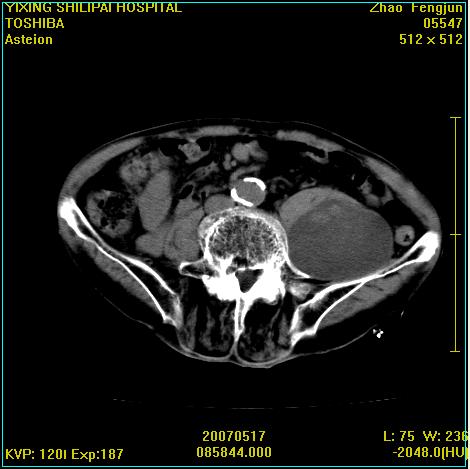

考虑:1、左侧腰大肌囊实性占位性病变(囊性神经根鞘瘤?);

2、右侧兰尾区囊性占位性病变(兰尾囊肿?囊腺癌?类癌?)

以下是引用xiaoniu在2007-5-26 10:45:00的发言:[br]腰大肌的病变应该没有问题,增强扫描还有轻度强化及细小血管影入内,应该排除脓肿,考虑占位性病变,腰大肌的占位多考虑:神经源性肿瘤。另外腹主动脉下端有真假腔的强化,考虑:主动脉夹层。[br][br][本贴已被 xiaoniu 于 2007-5-26 10:46:39 修改过]

以下是引用老爱克斯新网客在2007-5-26 18:26:00的发言:[br]1左下腹囊实性占位肿块,增强后不均匀强化,位于脊柱旁,椎体骨质无破坏软组织无肿胀,考虑神经源肿瘤神经鞘瘤可能大,2右下腹囊性占位性病变,增强后囊壁强化,考虑阑尾囊肿或囊腺瘤,